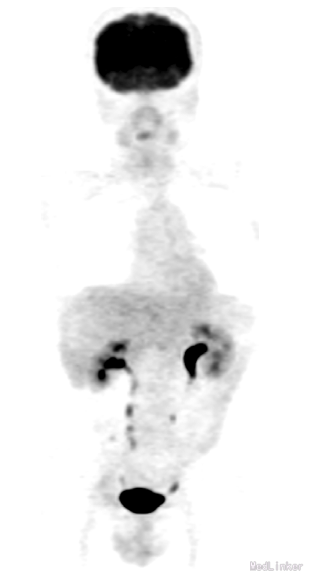

生化、肝功、肿瘤标记物(包括CA 19-9、AFP)检查未见异常。作为随访,患者每年进行一次影像学检查。在2005年进行的首次CT检查提示右肝一直径10cm囊肿(图1a),当时未见实性病变。2006年动态CT检查发现囊肿右背侧出现20mm大小轻度对比增强病变(图1b),且有逐渐增大、影响 囊肿的趋势(图1c-h)。由于回声强度呈可变性,考虑病变为血管瘤,因此继续观察而未行进一步检查。随着肿物不断增大,动态CT和MRI检查发现肿物呈不均匀强化。在T1WI、T2WI上分别呈均匀低信号、高信号(图2a、b),动脉相、门脉相及延迟相可见不均匀强化(图2c-e)。肝胆期提示界限清晰、均匀低密度、与厚囊肿壁相连的肿物(图2f),MR弥散成像则呈明显高信号(图2g)。PET检查示肿物呈低摄取,与周围正常肝组织相同,胸部未见异常摄取(图3)。